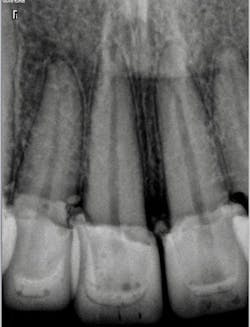

A 32-year-old male presented with having recent dental treatment abroad. Six maxillary anterior teeth had been individually crowned (figure 1).The patient’s chief complaint was severe pain in this area. He was unable to consume hot or cold food and drinks and could not use the teeth for incising. A radiographic exam revealed grossly overcontoured crowns, poorly fitting margins, and partially remaining cement (figure 2). The occlusion was evaluated and ruled out as the cause of pain. It was suspected after identifying the periapical radiolucency at the apex of the upper left lateral incisor that the pulps of some or all of the crowned teeth were affected.

Figure 2: Radiograph revealing overcontoured crowns, poorly fitting margins, and partially remaining cement